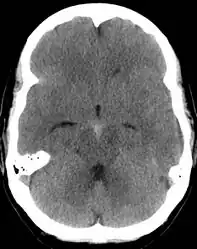

| CT scan of the brain showing subarachnoid hemorrhage as a white area in the center and stretching into the sulci to either side (marked by the arrow) | |